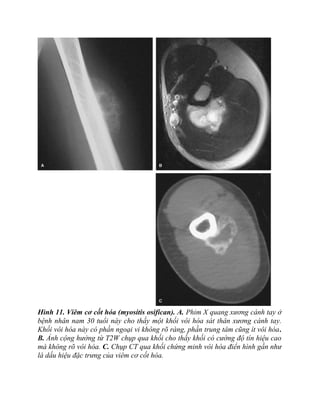

Hình 11. Viêm cơ cốt hóa (myositis osifican). A. Phim X quang xương cánh tay ở

bệnh nhân nam 30 tuổi này cho thấy một khối vôi hóa sát thân xương cánh tay.

Khối vôi hóa này có phần ngoại vi không rõ ràng, phần trung tâm cũng ít vôi hóa.

B. Ảnh cộng hưởng từ T2W chụp qua khối cho thấy khối có cường độ tín hiệu cao

mà không rõ vôi hóa. C. Chụp CT qua khối chứng minh vôi hóa điển hình gần như

là dấu hiệu đặc trưng của viêm cơ cốt hóa.